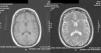

Case ReportThe patient was a 47-year-old woman diagnosed with SLE 10 years ago, with an outbreak of renal activity one year prior to admission that required treatment with mycophenolate mofetil (MMF) 3g daily, prednisone 1mg/kg with reduction to 0.5mg/kg/day, achieving disease activity remission. She was admitted with sudden onset headache, with an intensity of 9/10 on the visual analog scale, exacerbated with movement and no improvement with analgesics, accompanied by fever and nausea. Upon physical examination, she had no alterations in consciousness, impairment of higher mental functions or focal neurological data and presented negative meningeal signs. Study of the cerebrospinal fluid (CSF) showed leukocytes 27mm−3 (80% mononuclear), RBC 45mm−3, protein levels, normal CSF glucose, other tests and Gram stain were negative, IgM and IgG antibodies to cytomegalovirus and herpes virus were negative. Laboratory studies showed leukocytosis 13000cel./Mm3 with neutrophilia and monocytosis, low C3 levels with normal C4, elevated titers of anti-DNA, urinalysis with proteinuria, microhematuria and negative cylinders. The initial diagnosis was neuroinfection vs neuropsychiatric SLE activity; we began empirical treatment with ceftriaxone 2g every 12 h, vancomycin 1g every 12 h, acyclovir 600mg every 8 h, dexamethasone 8mg every 8 h. Magnetic resonance imaging (MRI) of the brain showed, on the frontal lobe, an injury consistent with a brain abscess (Fig. 1). At 48h the CSF was reported colorless, no leukocytes, erythrocytes 15, protein 39mg/dl and normal CSF glucose, PCR for M. tuberculosis was negative. After 4 days, LM growth was reported in the CSF, negative blood cultures, leading to a change in treatment ampicillin 2g intravenously every 4h for 6 weeks, with complete resolution without sequelae. A cerebral MRI after one month showed a nodular impregnation area 3mm diameter situated frontally with minimal adjacent edema. At 4 months there was evidence of the infectious process (Fig. 2).